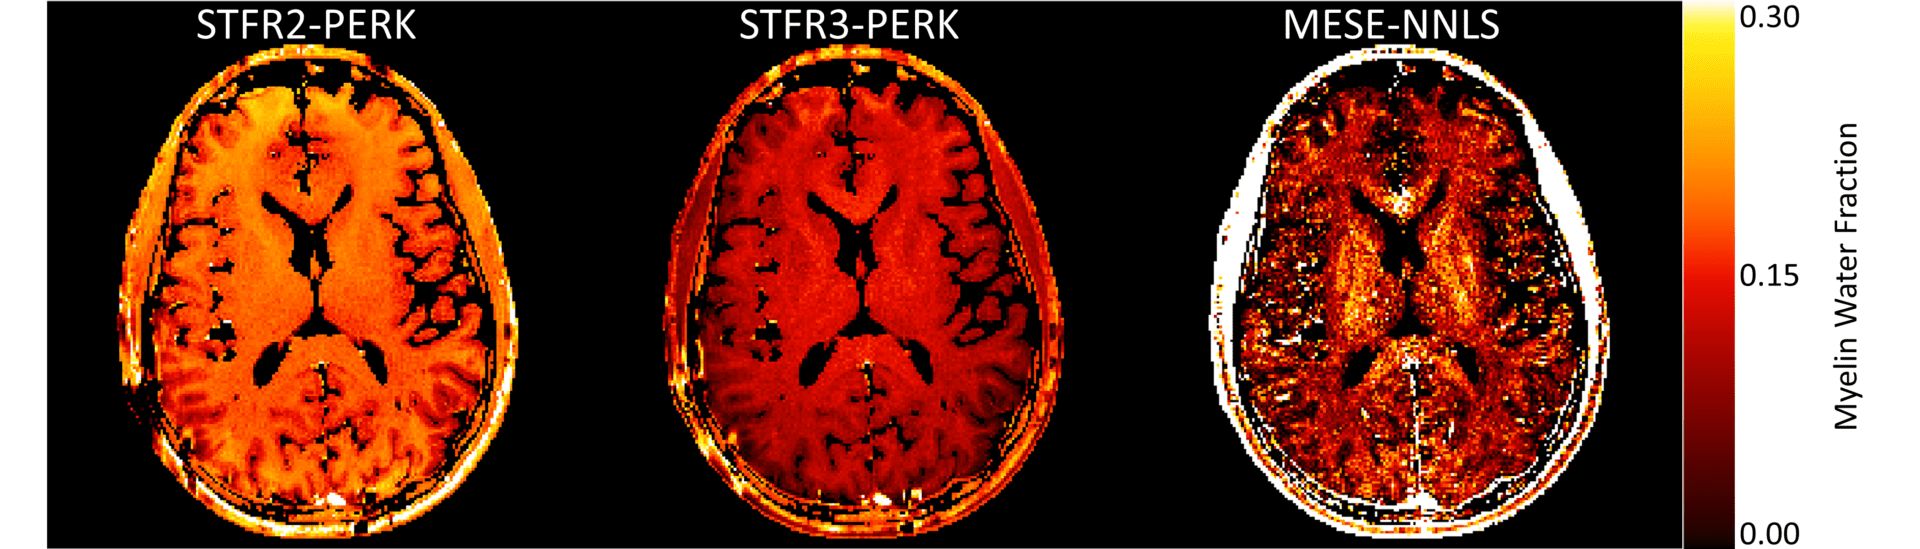

Magna cum Laude Merit Award for research to detect the progress of diseases such as multiple sclerosis

The researchers’ imaging technique is fast, accurate, and reproducible

Research to improve medical imaging of the brain receives Magna cum Laude Merit award

The interdisciplinary team was able to dramatically speed up the process while potentially doubling the quality of the image